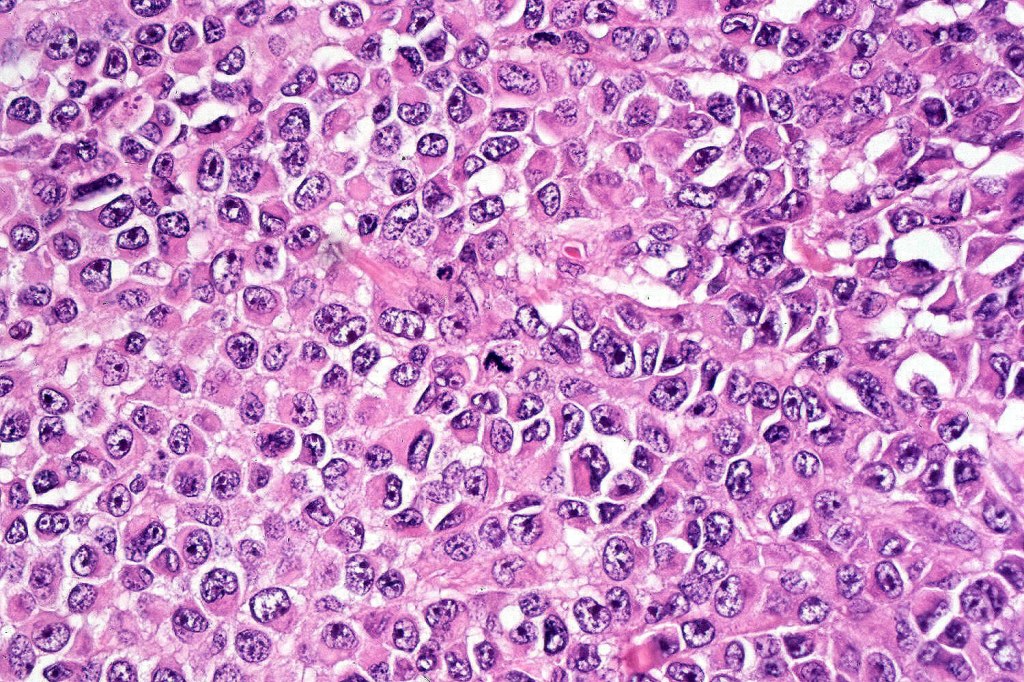

•Characterized by pleomorphic tumor cells with large eosinophilic, hyaline globular inclusions and eccentric vesicular nuclei containing prominent nucleoli, mitoses often conspicuous

•Inclusions predominantly composed of vimentin intermediate filaments

•Vimentin & sometimes desmin expression positive in the inclusions

•Very sparse melanin pigment may be identified